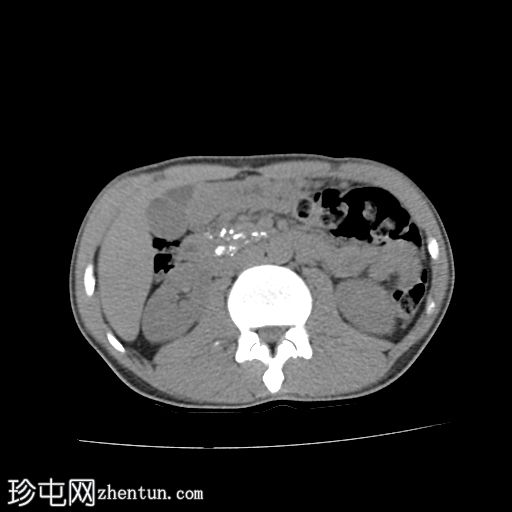

轴位

平扫

胰腺肿大。胰头、胰颈和胰体未见强化,边界不清且不规则。主胰管扩张,管内可见钙化。

胰腺实质内弥漫散在分布着大量钙化灶。

胰尾可见部分强化区域。

胰尾部钙化性假性囊肿。

影像学表现提示慢性钙化性胰腺炎伴胰尾部钙化性假性囊肿。